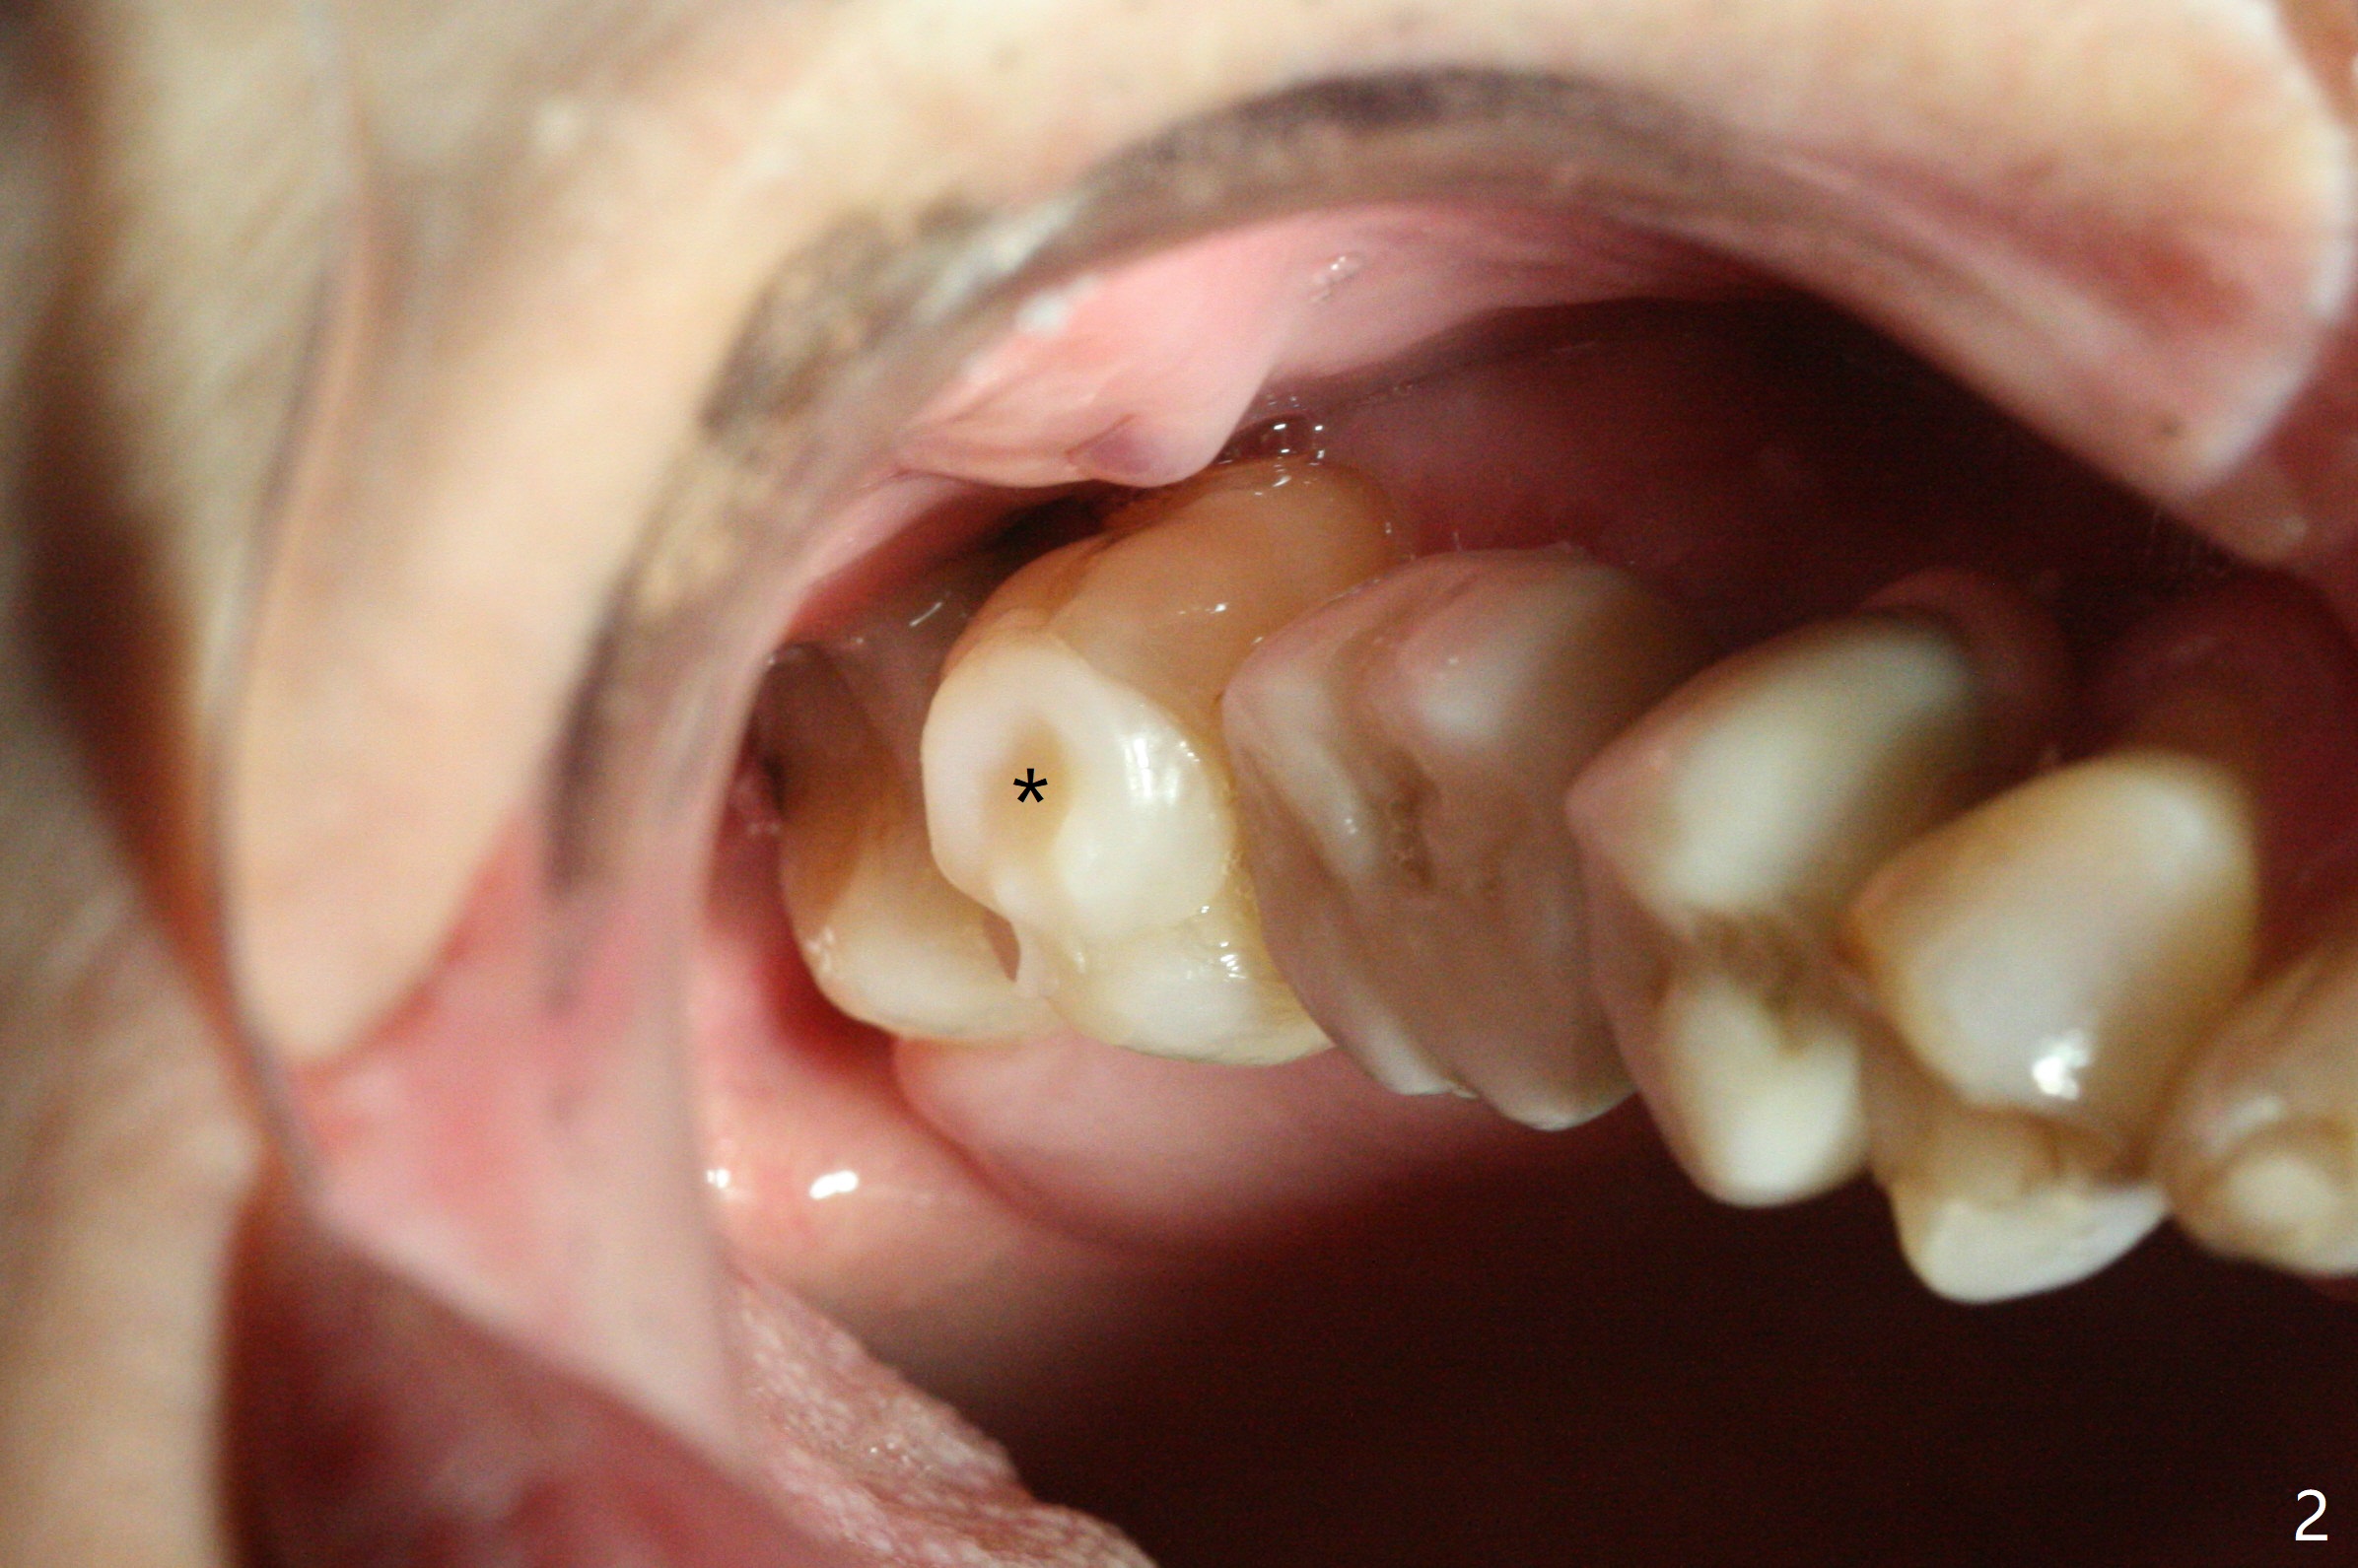

Two weeks post provisionalization over implants at #18 and 19 (4.5 months postop), acrylic is added to the provisional (Fig.1 *) and composite is placed on the other side (Fig.2 *) for clearance (Fig.3). Six days post bracketing, the diastema between LL5 and 6 decreases (Fig.4 between arrows, as compared to Fig.3), suggesting uprighting and distalization of the affected tooth. The diastema increases by trimming the mesial surface of LL6 provisional (Fig.5 *) prior to power chain placement. More acrylic is added to the occlusal surface of LL 6 and 7; more composite to that of UR3 (as compared to Fig.2) for clearance. Power chains change every week. LL5 is uprighted and distalized 1.5 months post banding (Fig.6,7 (14 niti)). Anterior brackets will be placed to correct LL2 cross bite next visit. Three weeks post open coil spring (5 months post initial banding), there is a space between LL2 and 3 (Fig.8) and between LL3/4 (Fig.9). The latter reduces instantly post power chain between LL3 and 6 (Fig.10). There is enough space for LL2 and sling shot is used to correct the cross bite 6.5 months post initial banding (Fig.11). The cross bite is corrected in 1.5 months after occlusal clearance is established (Fig.12). The lower left alignment is within normal limit, although in cross bite with the opposing dentition, immediate post molar crown cementation (Fig.13).